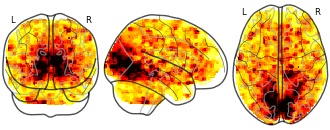

"name": "Multi_VBMgreater_fMRIenhanced",

"description": "Multi-modal analysis in BPD. Brain regions exhibiting greater gray matter and enhanced activation during emotion processing in BPD compared to healthy controls. Note: Results were thresholded at p<.0025. Note2: Results were updated (see Erratum for this publication).",